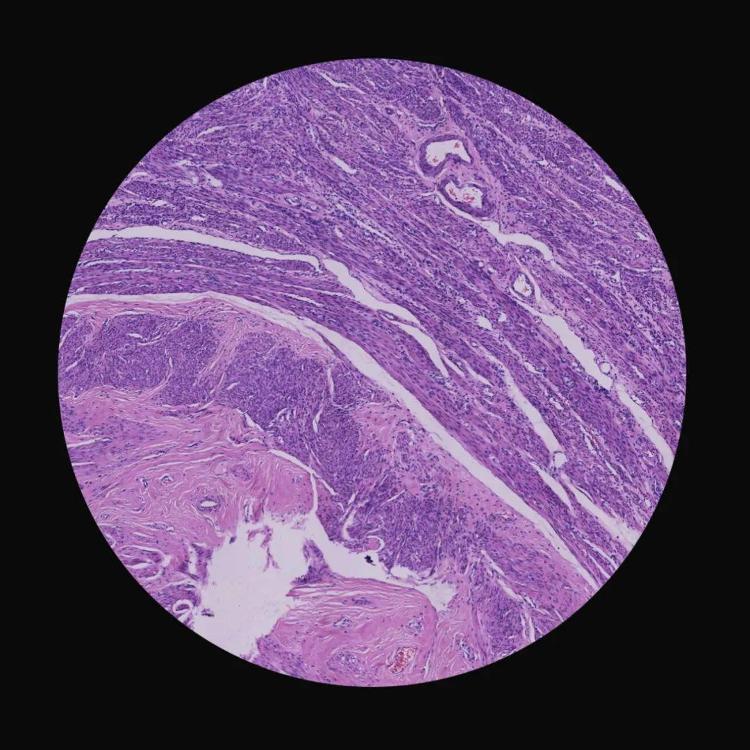

《生死较量》(组照) 李元鹏 摄影